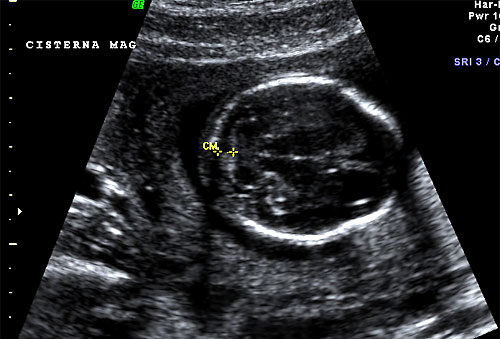

Normal 16 week cisterna magna |